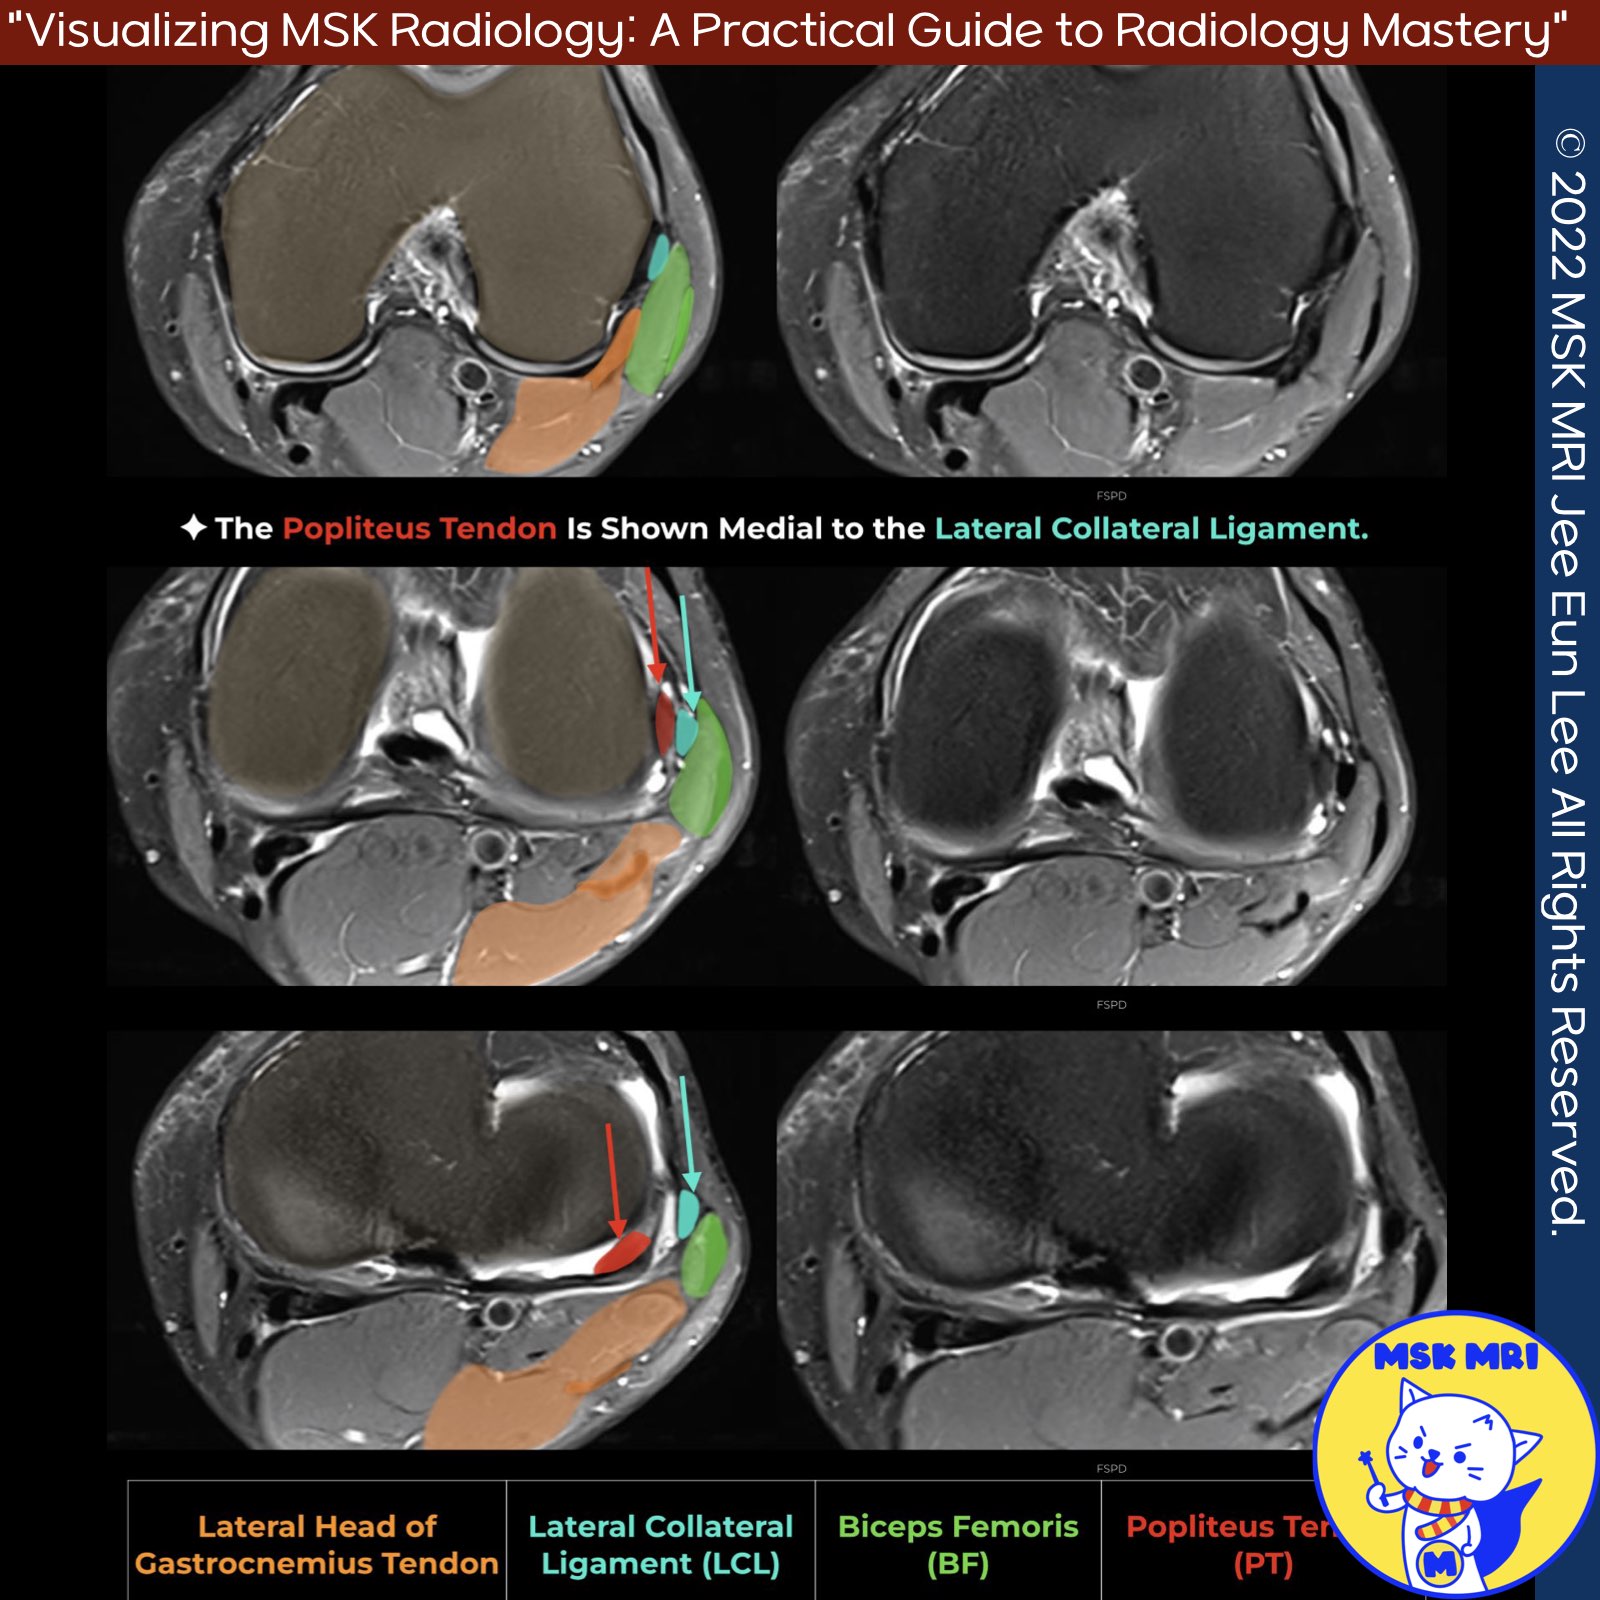

📌Anatomy of the Lateral Collateral Ligament (LCL) and Related Structures

- The lateral collateral ligament (LCL) originates from the lateral side of the distal femur in a fanlike fashion, attaching between the lateral epicondyle and supracondylar process, just proximal and posterior to the lateral epicondyle, and anterior to the lateral head of the gastrocnemius muscle.

- The LCL inserts on the lateral aspect of the fibular head, anterior and lateral to the fabellofibular and arcuate ligament attachments, and distal to the fibular styloid process tip.

- The lateral gastrocnemius tendon becomes adherent to the posterior knee capsule at the fabella level, inserting on the distal femur at the supracondylar process, just posterior to the LCL femoral attachment.

- Tendon The LCL and biceps femoris tendon blend into a conjoined tendon distally, inserting onto the fibular head.

- The popliteus tendon attaches to the lateral femoral condyle anterior and distal to the LCL femoral origin.

- On coronal images, the popliteus insertion is seen below the lateral gastrocnemius and LCL origins.

- The lateral femoral condylar groove allows its posterior course.